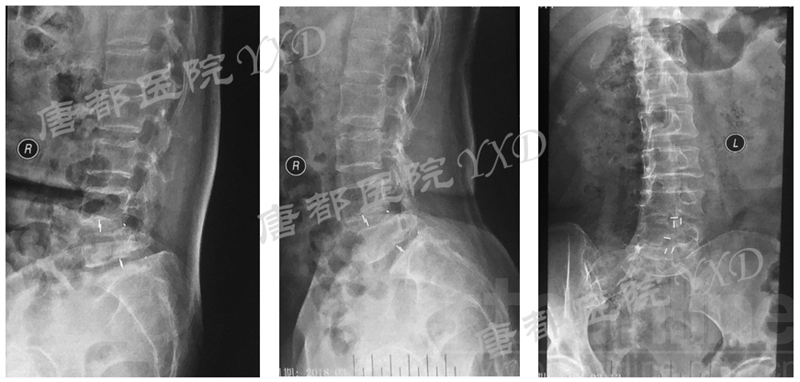

患者60岁,女性。

主诉:腰椎术后左下肢疼痛9月、加重4月。

专科情况:轮椅推入病房;强迫体位;双侧直腿抬高试验、加强试验阴性;左小腿后、外侧及足背、足底皮肤感觉减退;余未见明显异常。VAS评分:左下肢7。

既往8年前因“腰4、5椎弓峡部裂并腰4椎体滑脱症”于外院行腰4~骶1椎板减压椎间植骨融合内固定术,后因椎弓根螺钉断裂于5年前行内固定取出术。

影像学检查:

诊断:腰椎椎间融合术后融合器后移

手术方案:显微镜辅助MI-TLIF腰椎翻修术

术中视频:http://api.orthonline.com.cn/attach/Case3.mp4(术中发现因前次手术全椎板及关节突切除,TLIF的第一步,即关节突关节的定位落脚点难以找到。显微镜下通过Kambin三角解剖位置,进行从外至内的解剖,寻找cage尾端;此外,因大量瘢痕渗血,难以进行充分止血;但在显微镜的照明和放大视野下,操作均可在不伤及神经的前提下进行。由于终板骨质吸收,椎间隙塌陷,导致术野内可同时看到出行根和走行根。而在显微镜下,能够通过调整景深和视线角度,精准充分处理椎间隙骨性终板。无手术并发症)